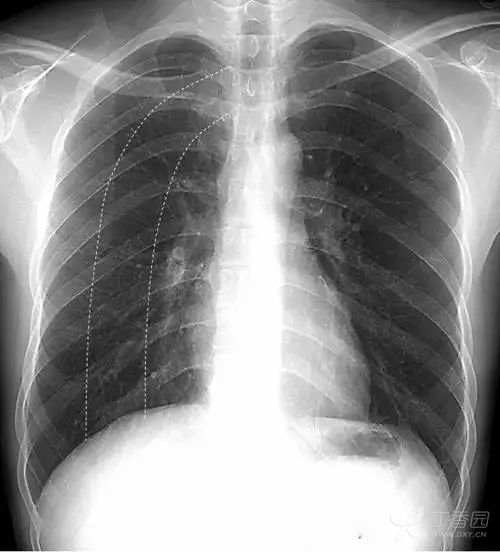

在解剖结构上,肺叶由叶间裂胸膜自然分隔而成,左肺由斜裂分为上、下2个叶,右肺由水平裂(横裂)和斜裂分上、中、下3个叶。胸部X线平片中,叶间裂胸膜和X线方向平行时可以显影,呈细线状。其中,正位胸片常可以看到右肺水平裂(图11)。

图11 右肺水平裂。正位胸片常可以看到细线状的右肺水平裂,位于右肺野中部,自肺野边缘向右肺门水平走行,水平裂以上为右肺上叶,以下为右肺中叶和下叶。